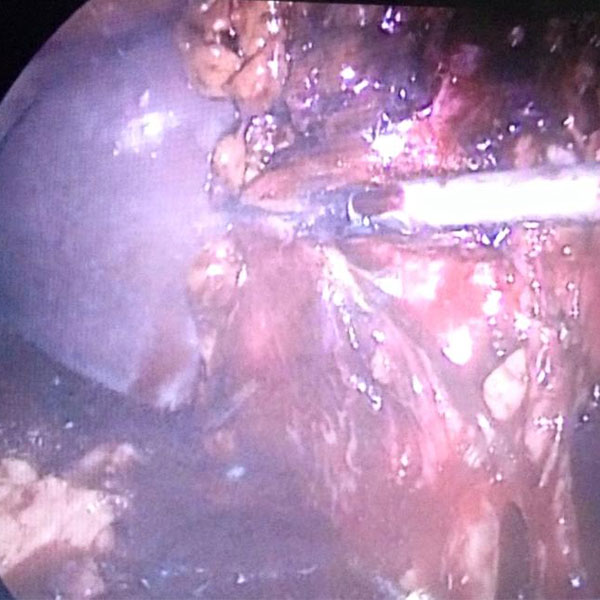

60 yr old male known case of gall stone pancreatitis multiple episode since last year came with last episode 6 weeks back was treated conservatively now came for elective cholecystectomy . It was a badly frozen gall bladder area but with patience i was able to perform it laparoscopically , nt to forget the imp of gud asistance by my colleaque